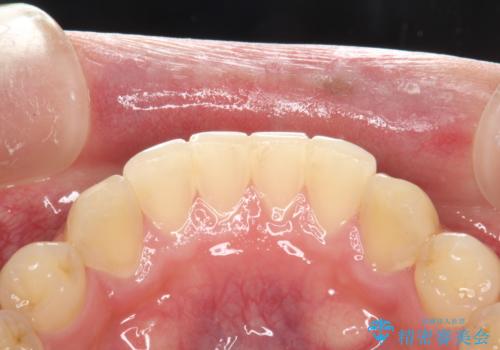

- 半年ぶりの来院で、全体的なチェックとクリーニング希望でした。PMTC(自費クリーニング)60分コースを行いました。

PMTCとは、プロフェッショナル(歯科衛生士)メカニカル(機械的)トゥース(歯)クリーニング(清掃)の略です。歯科医院にて、いろいろな機械・材料を使用し汚れを落とします。

磨き残しや、細菌は歯の表面がザラザラしている部分につきやすいです。そのためPMTCを定期的に繰り返すことで、歯の表面がツルツルの状態である期間が長くなるため、虫歯や歯周病予防につながります。